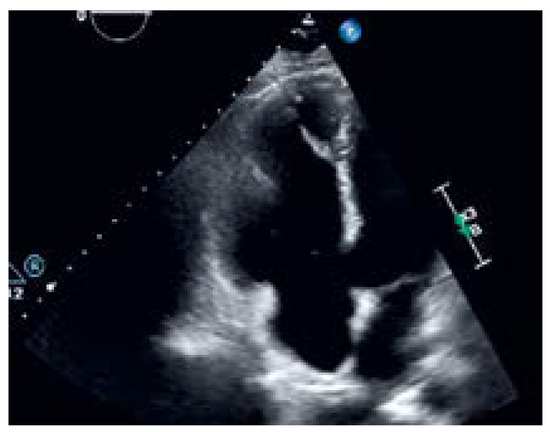

Sinus Venosus Atrial Septal Defect with Partial Anomalous Pulmonary Vein Return

by Renata Wojtal, Andres Spirig, Tim Ohletz, Laurent M. Haegeli and Tobias A. Fuchs

Cardiovasc. Med. 2022, 25(4), 124; https://doi.org/10.4414/cvm.2022.02215 - 1 Jul 2022

We report a 44-year-old patient, who was initially referred for routine cardiac evaluation, because of family history of sudden cardiac death and a probable new onset of a right bundle branch block (RBBB) on a regular electrocardiogram (ECG) (fig. 1). [...] Full article